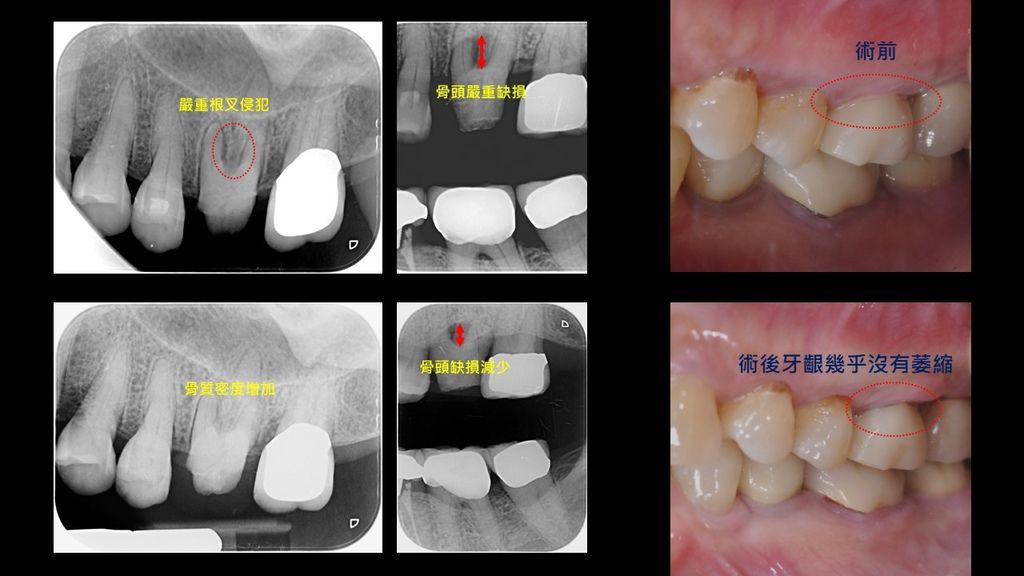

像這個病人左上第一大臼齒嚴重根叉侵犯,牙齒鬆動,在顯微鏡下以水雷射輔助進行牙周微創再生手術(微光牙醫02-23258678莊邦寧醫師),從影片中可以看得出來傷口非常小,確實達到傷口最小化癒合最佳化的治療效果

手術後6個月後骨質明顯增加,無動搖度,而且牙齦幾乎沒有萎縮,可以減少牙根敏感與清潔不易的問題